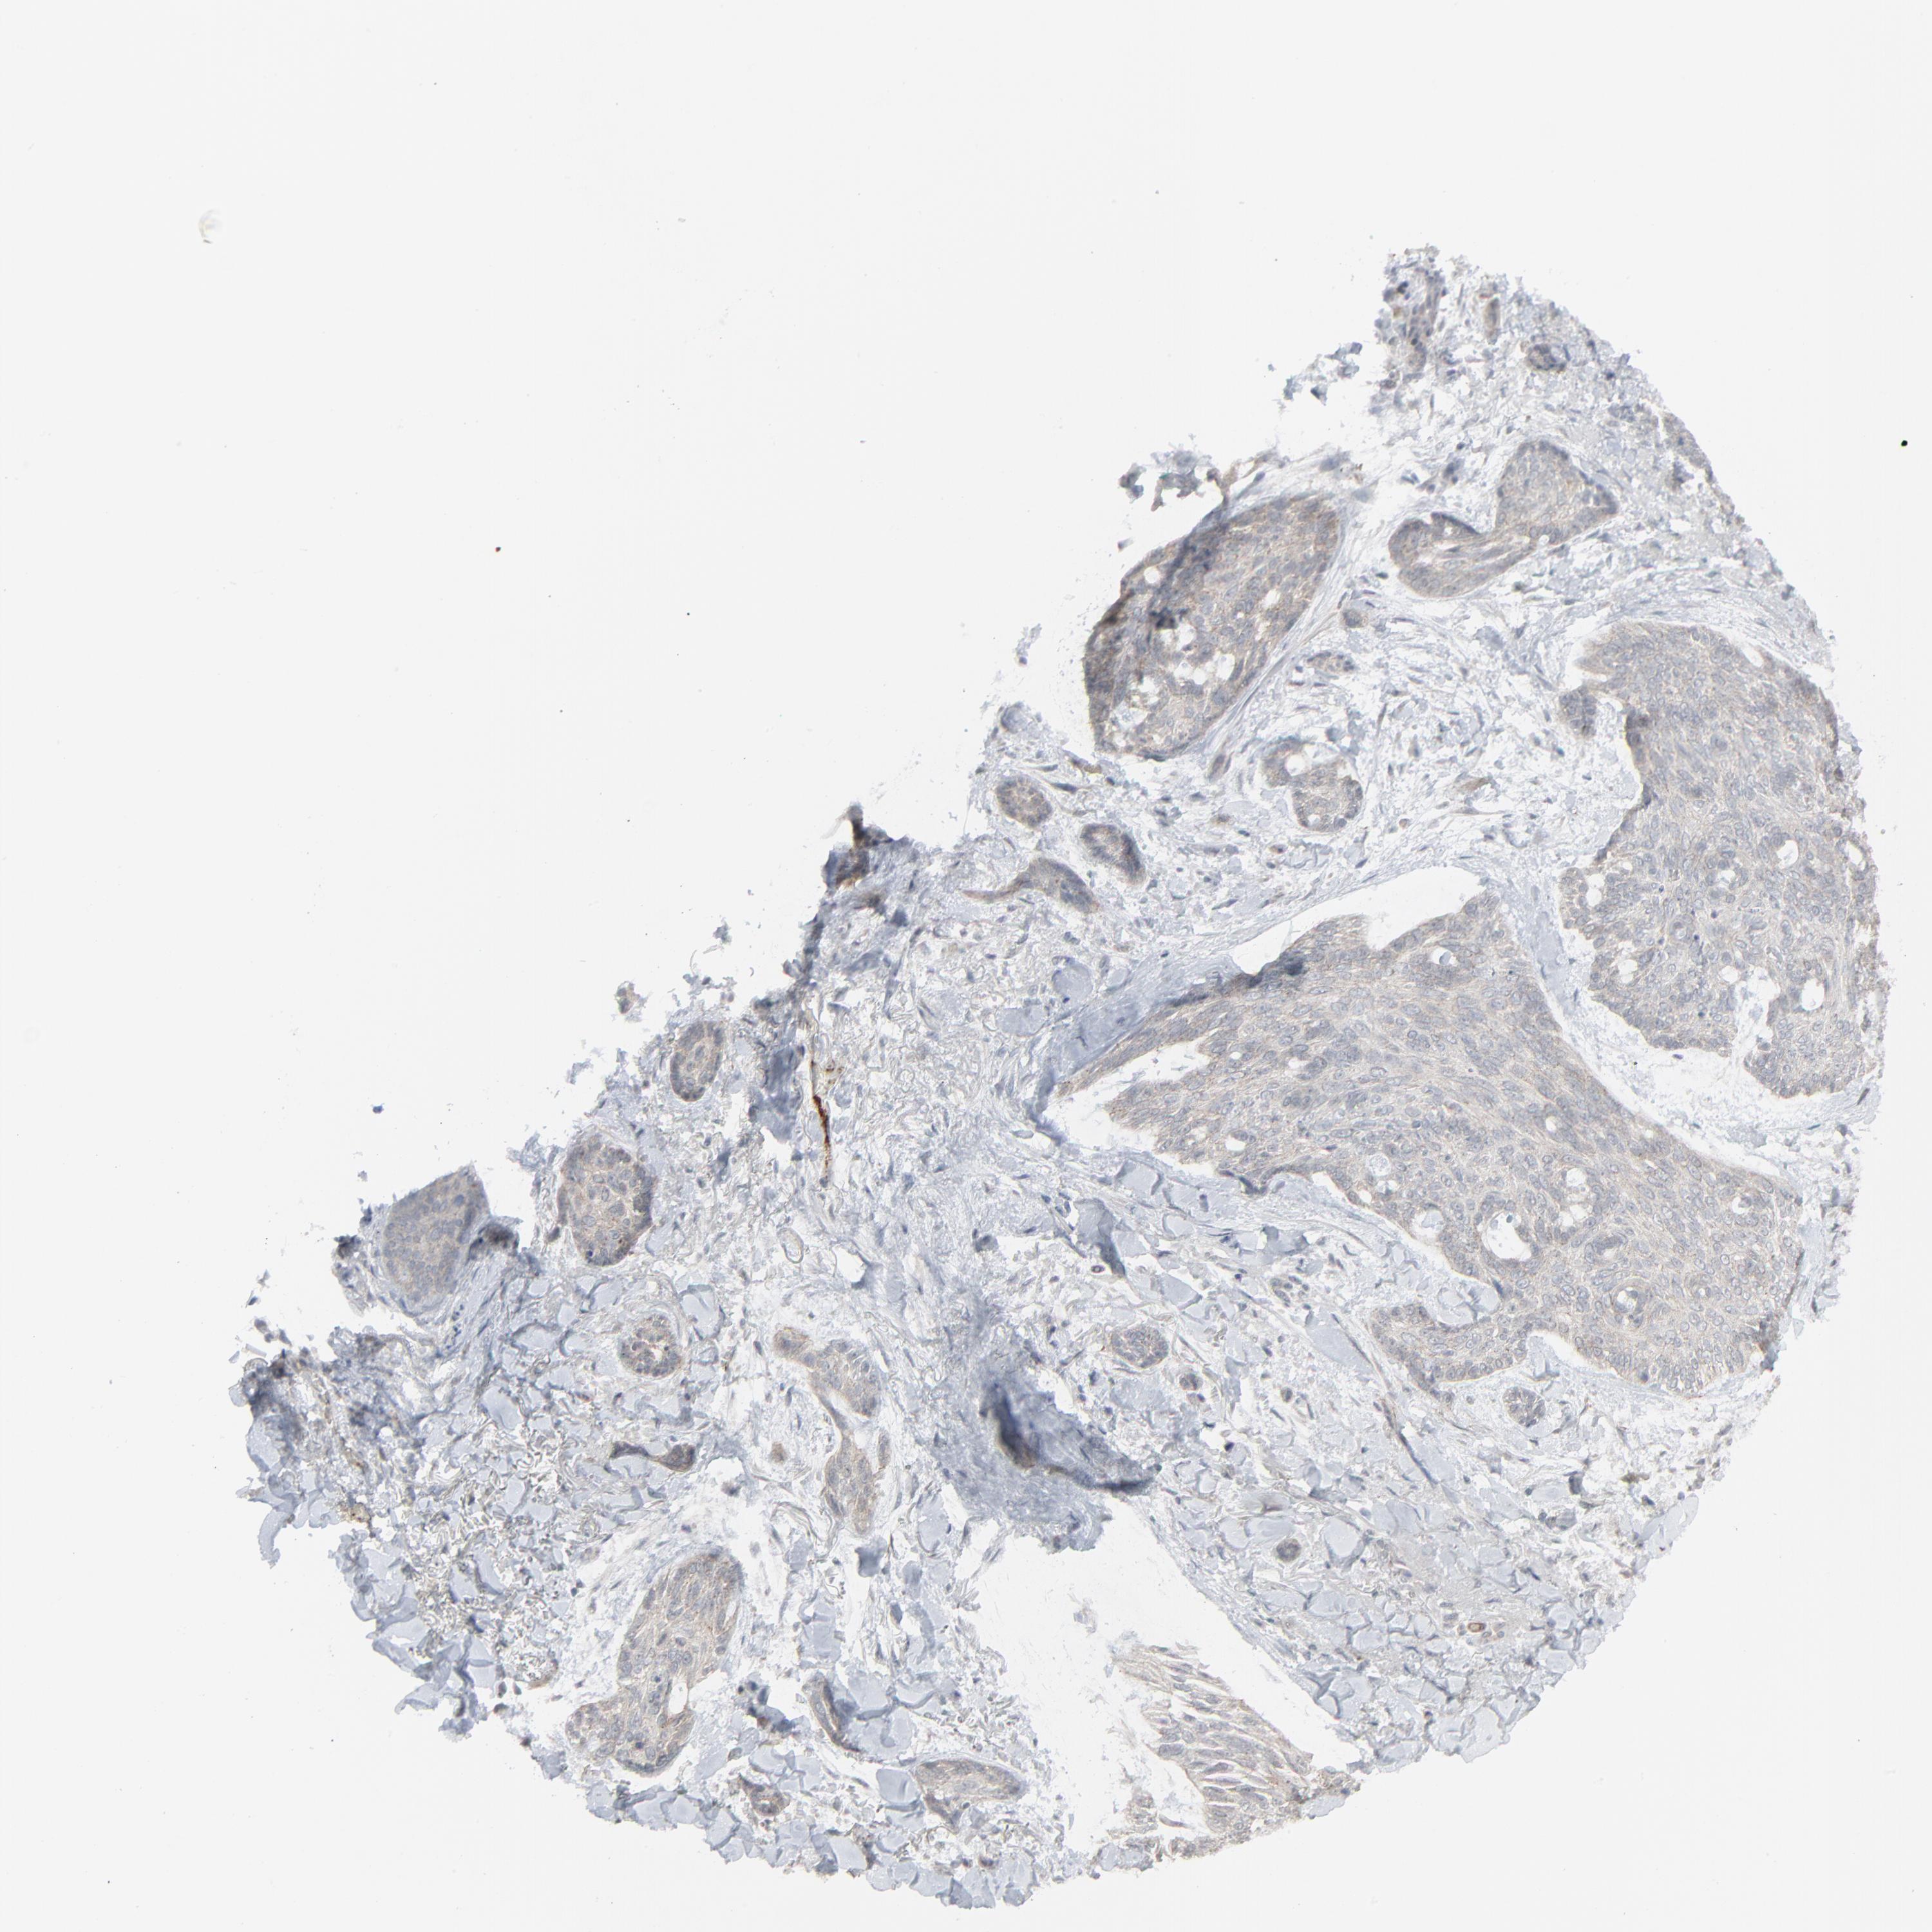

Basal cell and squamous cell cancer

SKIN CANCER - Protein expressioni

A mouse-over function shows sample information and annotation data. Click on an image to view it in a full screen mode. Samples can be filtered based on level of antibody staining by selecting one or several of the following categories: high, medium, low and not detected. The assay and annotation is described here.

Antibody stainingi

Antibody staining in the annotated cell types in the current human tissue is reported as not detected, low, medium, or high, based on conventional immunohistochemistry profiling in selected tissues. This score is based on the combination of the staining intensity and fraction of stained cells.

Each image is clickable and will lead to virtual microscopy that enables deeper exploration of all samples and also displays staining intensity scores, fraction scores and subcellular localization as well as patient and tissue information for each sample.

Antibody HPA003278

Antibody CAB022450

Staining

High

Medium

Low

Not detected

Intensity

Strong

Moderate

Weak

Negative

Quantity

>75%

75%-25%

<25%

None

Location

Nuclear

Cytoplasmic/membranous

Cytoplasmic/membranous,nuclear

Squamous cell carcinoma, NOS

Basal cell carcinoma